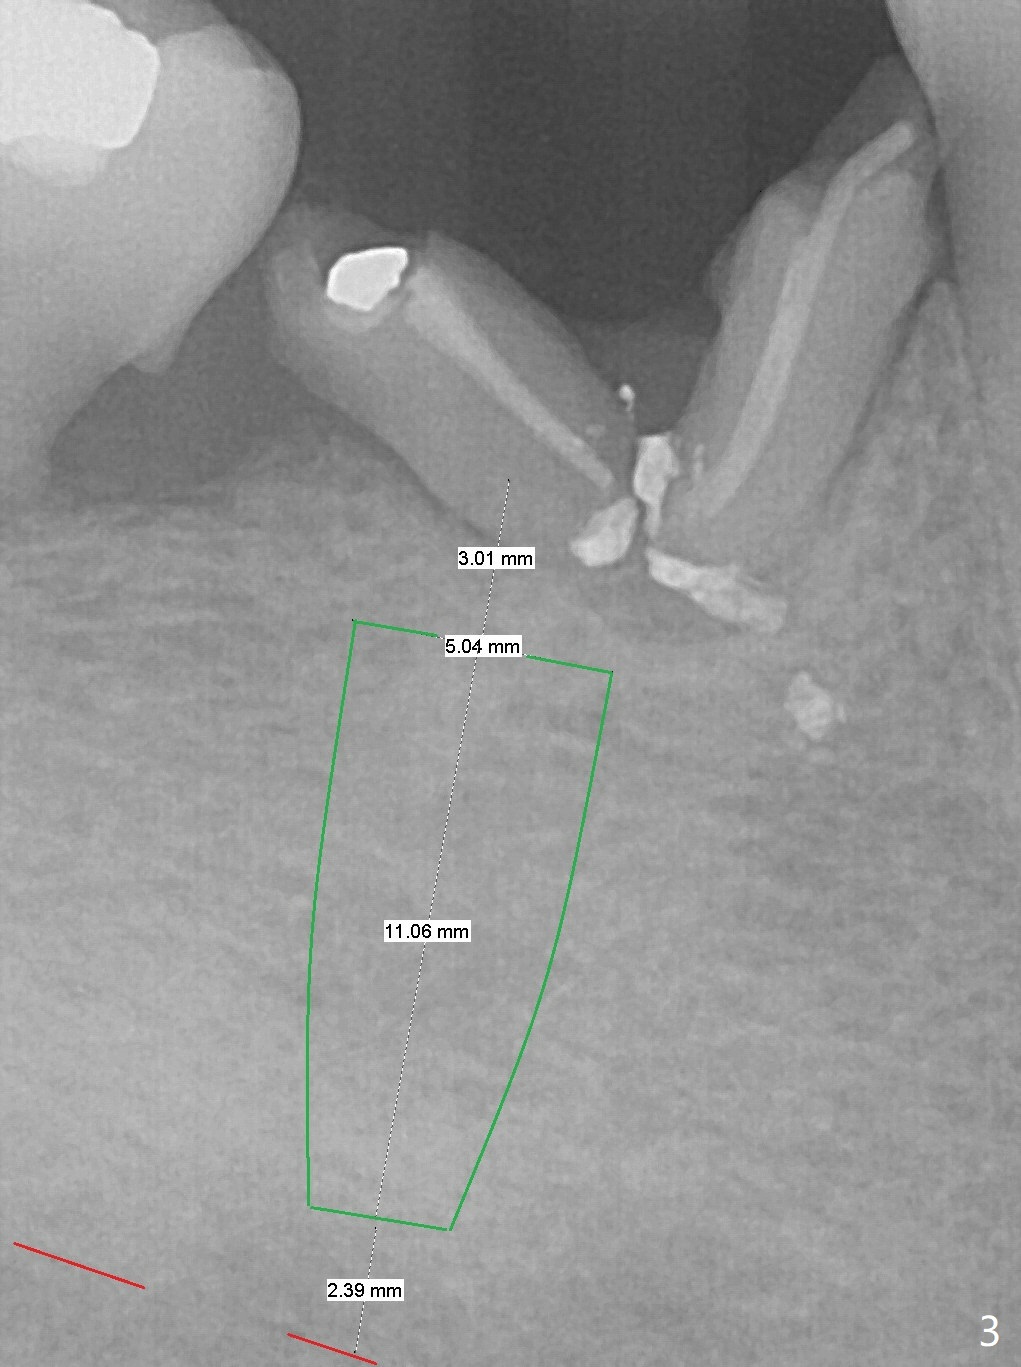

A 50-year-old man has poor dentition, including residual roots at #30 (Fig.1). In 9 years, the residual roots have migrated coronally (Fig.2 arrow). It appears that the bone height increases. Insert periodontal dressing into the mesial undercut of the tooth #31 (post scaling) and around an abutment for retention. Try IS implants if they arrive.